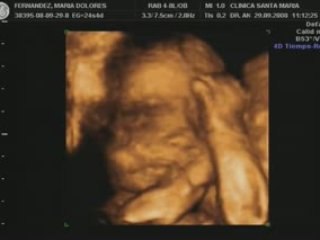

Ecografia Ostetrica 20 settimane